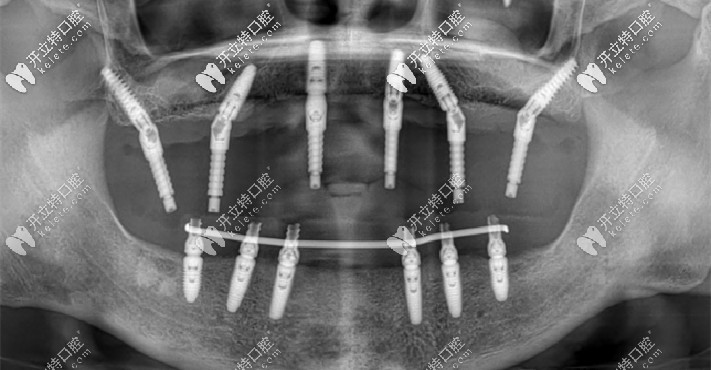

穿顴穿翼種植技術(shù)

上海鼎植口腔穿顴穿翼種植技術(shù)▲